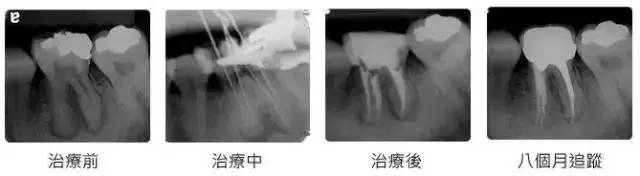

根管治疗时,拍牙片是很有必要的,并且至少要保证3张牙片。

第一张在治疗前,帮助医生了解牙根的基本情况,制定治疗计划;

第二张在治疗中,帮助医生了解治疗情况,如根管预备是否到位等,并制定下一步治疗方案;

第三张是在治疗结束后,帮助判定根管充填质量,发现问题及时补救。